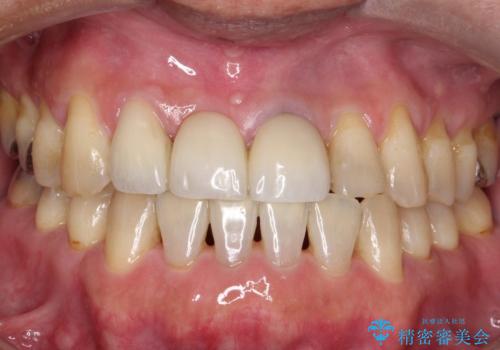

[根管治療・セラミッククラウン] 前歯の痛み・見た目を改善したい

![[根管治療・セラミッククラウン] 前歯の痛み・見た目を改善したいの症例 治療後](https://seimitsushinbi.jp/wp/wp-content/uploads/2021/10/969aa8878a18bb42608c420b34b6b67f-500x350.jpg?v=1633830182)